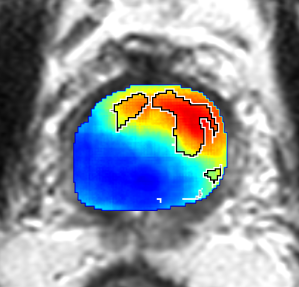

Qualitative Evaluation: Figure 4 shows the same slice as in Figure 2 with aligned T2W, ADC, and histopathology images, and prediction results using current state-of-the-art method [4], our CorrSigNet() and CorrSigNet(T2W, ADC, ) models. It may be noted that [4] fails to detect the cancerous regions on the left and right of the images, while the CorrNet representations alone can identify the cancer regions, and when combined with T2W and ADC images, they predict the cancer regions with high probability. It may also be noted that CorrSigNet(T2W, ADC, ) shows fewer false positives than [4]. This example shows the strength of learning correlated MRI signatures in identifying subtle, and sometimes MRI-invisible cancers. Figure 5 shows more example slices from different patients, comparing the state-of-the-art approach [4] and our prediction results with CorrSigNet(T2W, ADC, ). We note that our model with correlated features (1) can identify subtle and smaller cancer regions, (2) have better overlap with ground truth cancer labels, and (3) have fewer false positives.